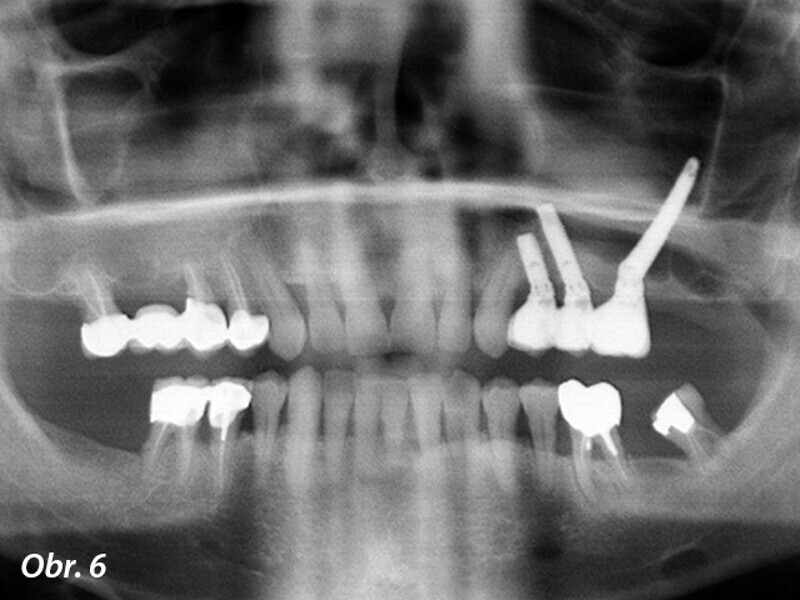

Rehabilitace unilaterální maxilární bezzubosti